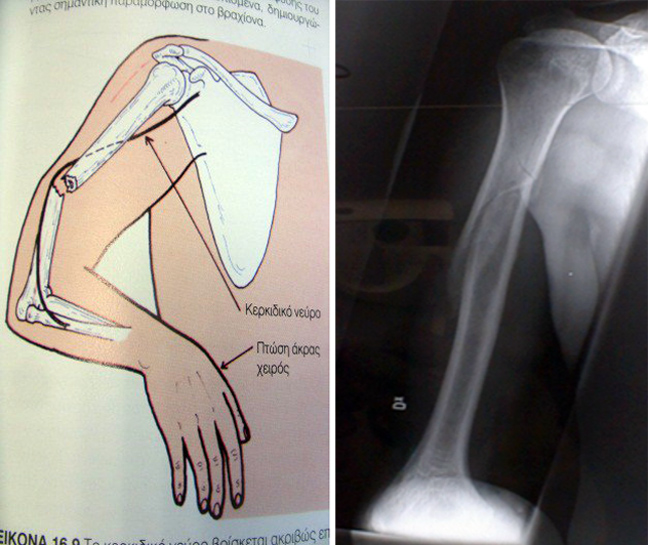

Μερικές φορές, όταν το κάταγμα συμβεί στη μέση του βραχιονίου οστού (εικόνα 1) μπορεί να πιεσθεί το κερκιδικό νεύρο, που περνάει δίπλα και να εμφανίσει το χέρι πάρεση (παράλυση).

Ελέγχουμε τη δυνατότητα του τραυματισμένου να κάνει «auto-stop» με τον αντίχειρα. Εάν αδυνατεί, το νεύρο πιέζεται και το κάταγμα χρειάζεται χειρουργείου οπωσδήποτε.